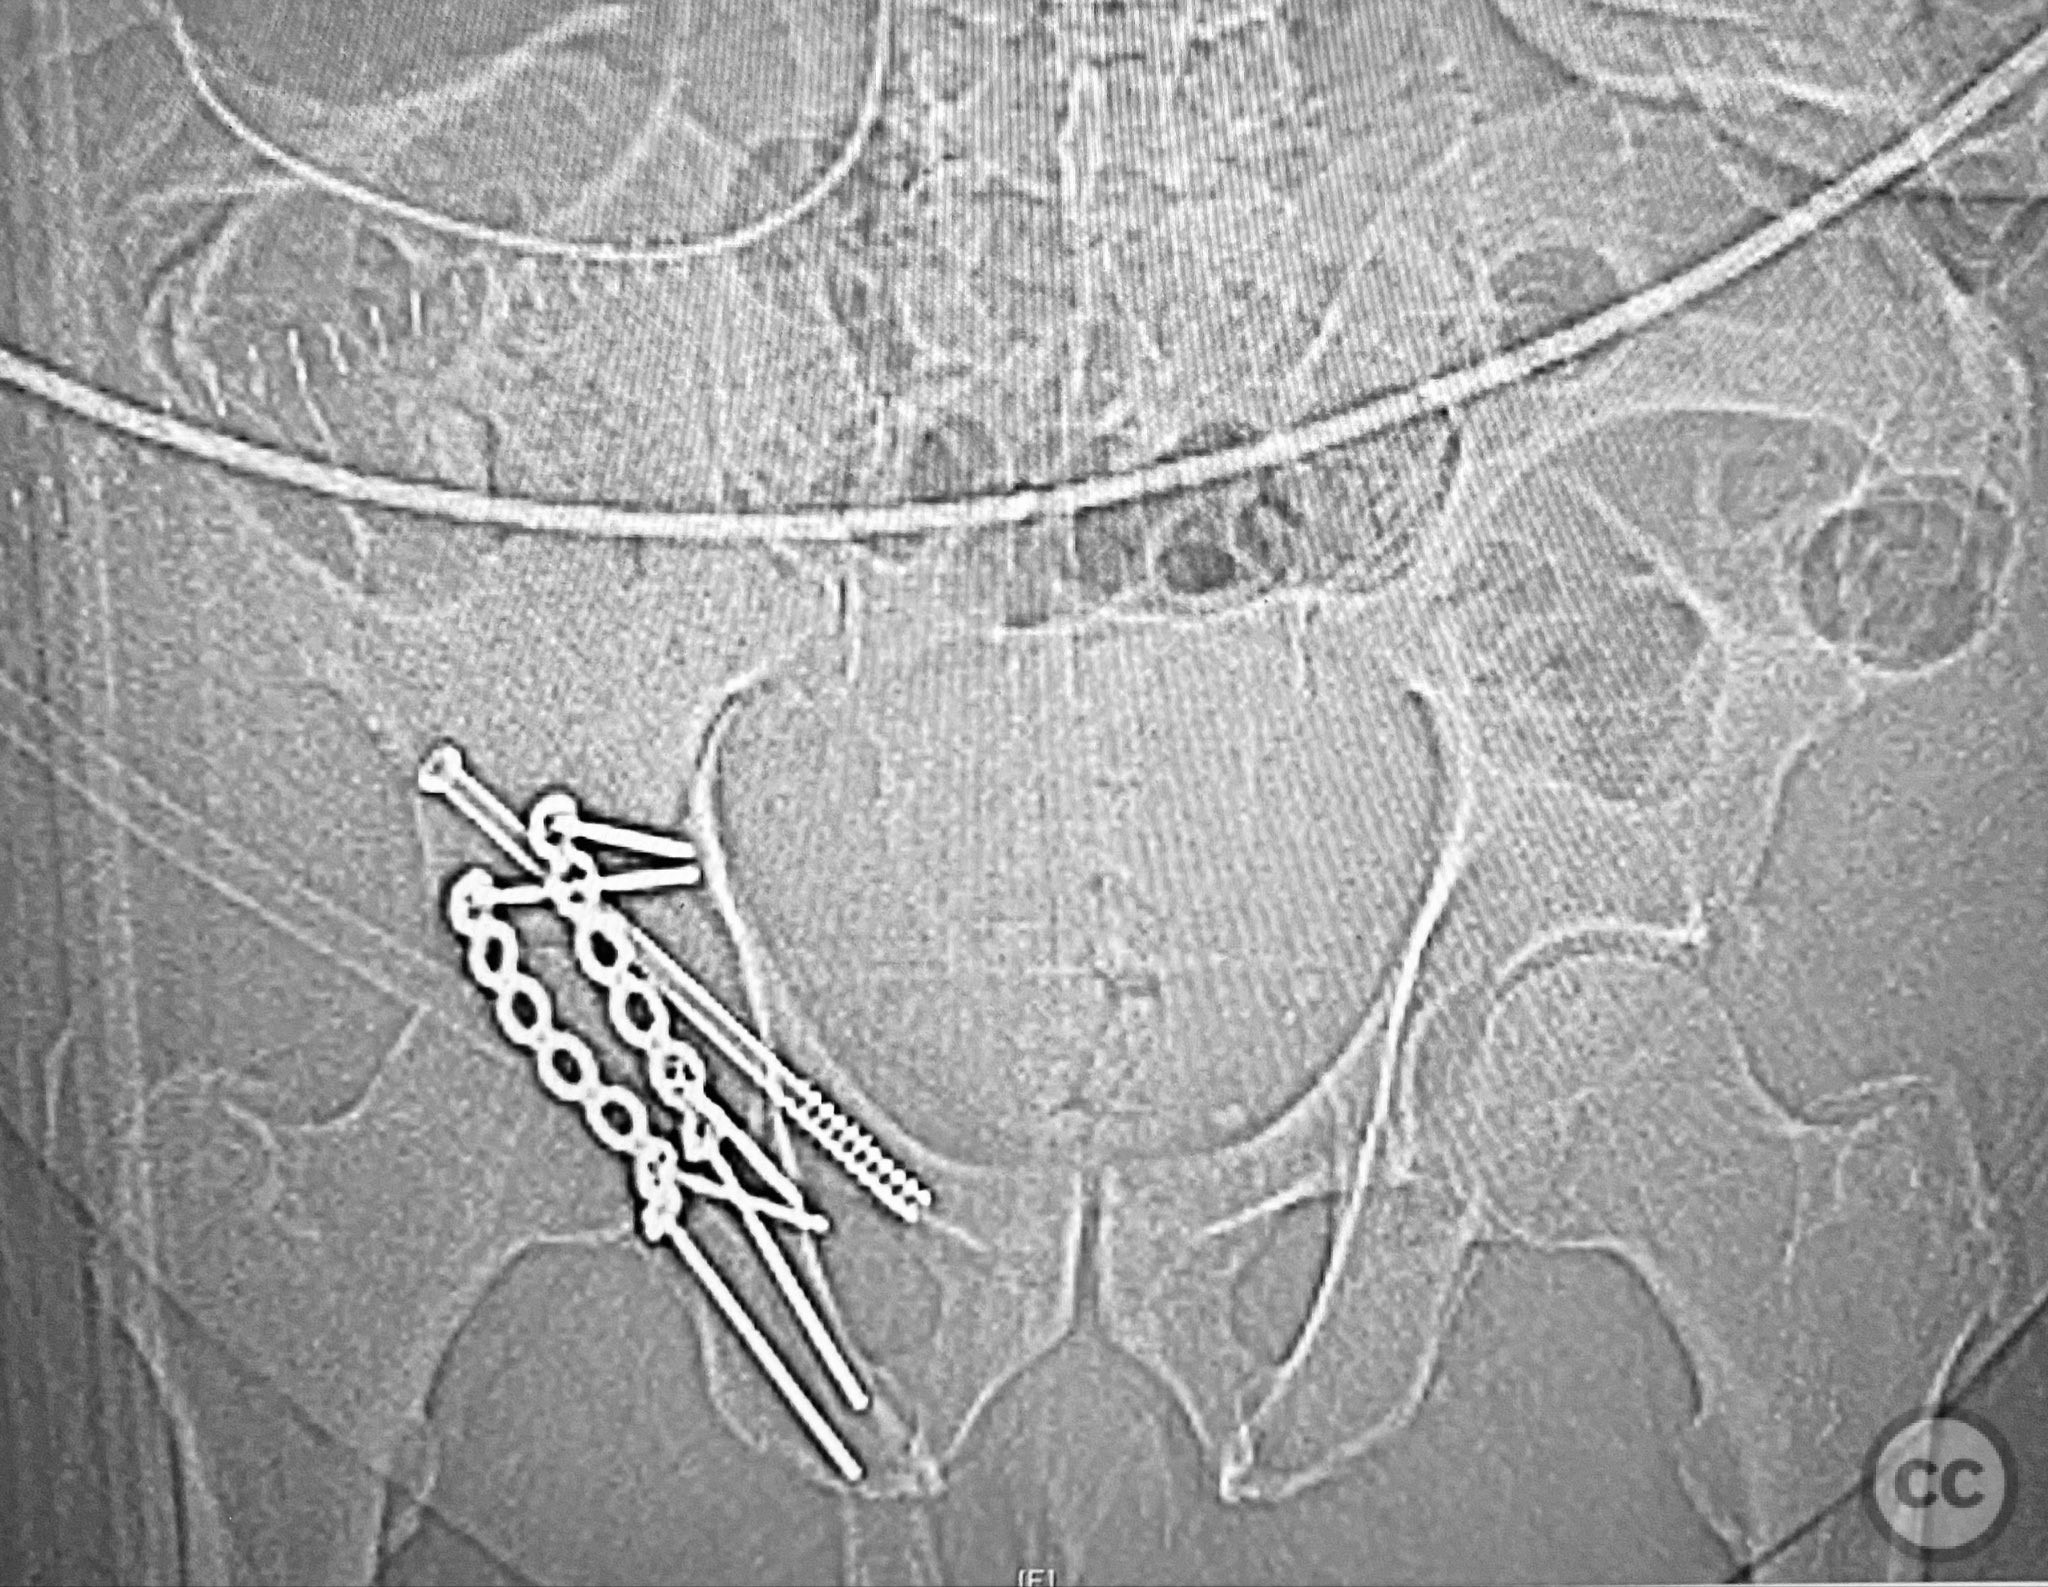

Anatomical surgical approach:  A standard Kocher-Langenbeck approach was performed, incising through the gluteal fascia and splitting the fibers of the gluteus maximus. The short external rotators were identified and protected, with subperiosteal dissection exposing the posterior column and wall of the acetabulum. The sciatic nerve was identified and mobilized laterally. The posterior capsule was found disrupted adjacent to the intact articular surface. The impacted osteochondral fragment was extracted from the joint space. The transverse fracture plane was debrided and reduced using clamps, with a greater trochanteric bone hook employed to manipulate the femoral head beneath the acetabular dome during reduction. Provisional fixation was achieved with a percutaneous lag screw across the transverse component. The peripheral posterior wall fragment was anatomically reduced and stabilized with a contoured plate. The medial wall defect provided access for reduction of the impacted articular segment, which was bone grafted prior to reduction and plating of the medial wall. Capsular tissues were repaired with nonabsorbable sutures prior to layered wound closure.

The posterior wall fragments exhibited an unusual caudal hinge morphology, necessitating careful mobilization to avoid propagation or comminution. Removal of the impacted intra-articular fragment was essential to achieve concentric reduction of the femoral head within the acetabular dome. Use of a greater trochanteric bone hook facilitated precise control of femoral head position during reduction maneuvers. The medial wall fragment, though non-articular, allowed direct visualization and accurate reduction of the impacted osteochondral segment, which was supported with bone graft prior to definitive fixation. Repair of disrupted capsular tissues was performed to restore soft tissue integrity and potentially reduce postoperative instability.

Orthopaedic implants used:   3.5mm pelvic reconstruction plate (posterior wall), 3.5mm pelvic reconstruction plate (medial wall), percutaneous cannulated lag screw, cancellous bone graft